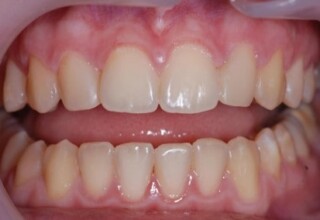

Οι όψεις πορσελάνης είναι ο καλύτερος τρόπος αντιμετώπισης αισθητικών προβλημάτων στην πρόσθια περιοχή του στόματος. Συνδυάζουν συντηρητική αφαίρεση οδοντικής ουσίας και πολύ υψηλή αισθητική απόδοση. Στο παρακάτω εκτεταμένο περιστατικό υπήρχαν: παλαιά σφραγίσματα, δυσχρωμίες, κακό σχήμα και μήκος δοντιών, κακή αναλογία δοντιών-ούλων. Έγινε προσεκτικός εργαστηριακός σχεδιασμός σε εκμαγεία απ’όπου προέκυψαν προσωρινές όψεις που τοποθετήθηκαν στο στόμα για δοκιμή και διορθώσεις. Όταν οριστικοποιήθηκαν οι μετατροπές, οι προσωρινές χρησιμοποιήθηκαν σαν οδηγός για τις μόνιμες. Οι πέντε μόνιμες όψεις πορσελάνης που κατασκευάστηκαν για τα πέντε πρόσθια δόντια της άνω απεκατέστησαν σχεδόν άψογα την αισθητική εμφάνιση της ασθενούς.